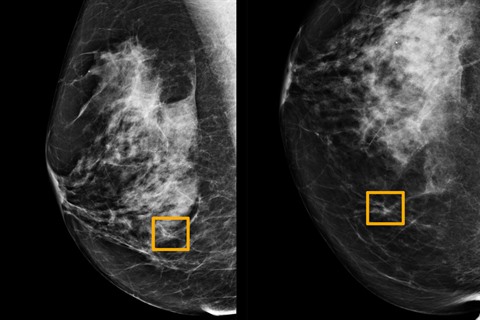

| Une patiente pendant une mammographie à l'institut Paoli-Calmette à Marseille. |

Cette technique d'intelligence artificielle (IA) issue de la recherche de Google est basée sur un modèle mathématique, un algorithme. Ce dernier a été entraîné, nourri, avec près de 29.000 images de mammographies provenant de Grande-Bretagne et dans une moindre mesure des États-Unis.

Les experts avaient accès aux antécédents de la patiente lors de l'interprétation des images radiographiques, alors que l'IA n'avait accès qu'à la dernière mammographie. L'IA a montré une réduction de la proportion de cas où un cancer a été détecté à tort, de 5,7% sur les images américaines étudiées et de 1,2% sur les britanniques. L'algorithme a également réduit le pourcentage de diagnostics manqués de 9,4% parmi les images américaines et 2,7% parmi celles provenant de Grande-Bretagne.